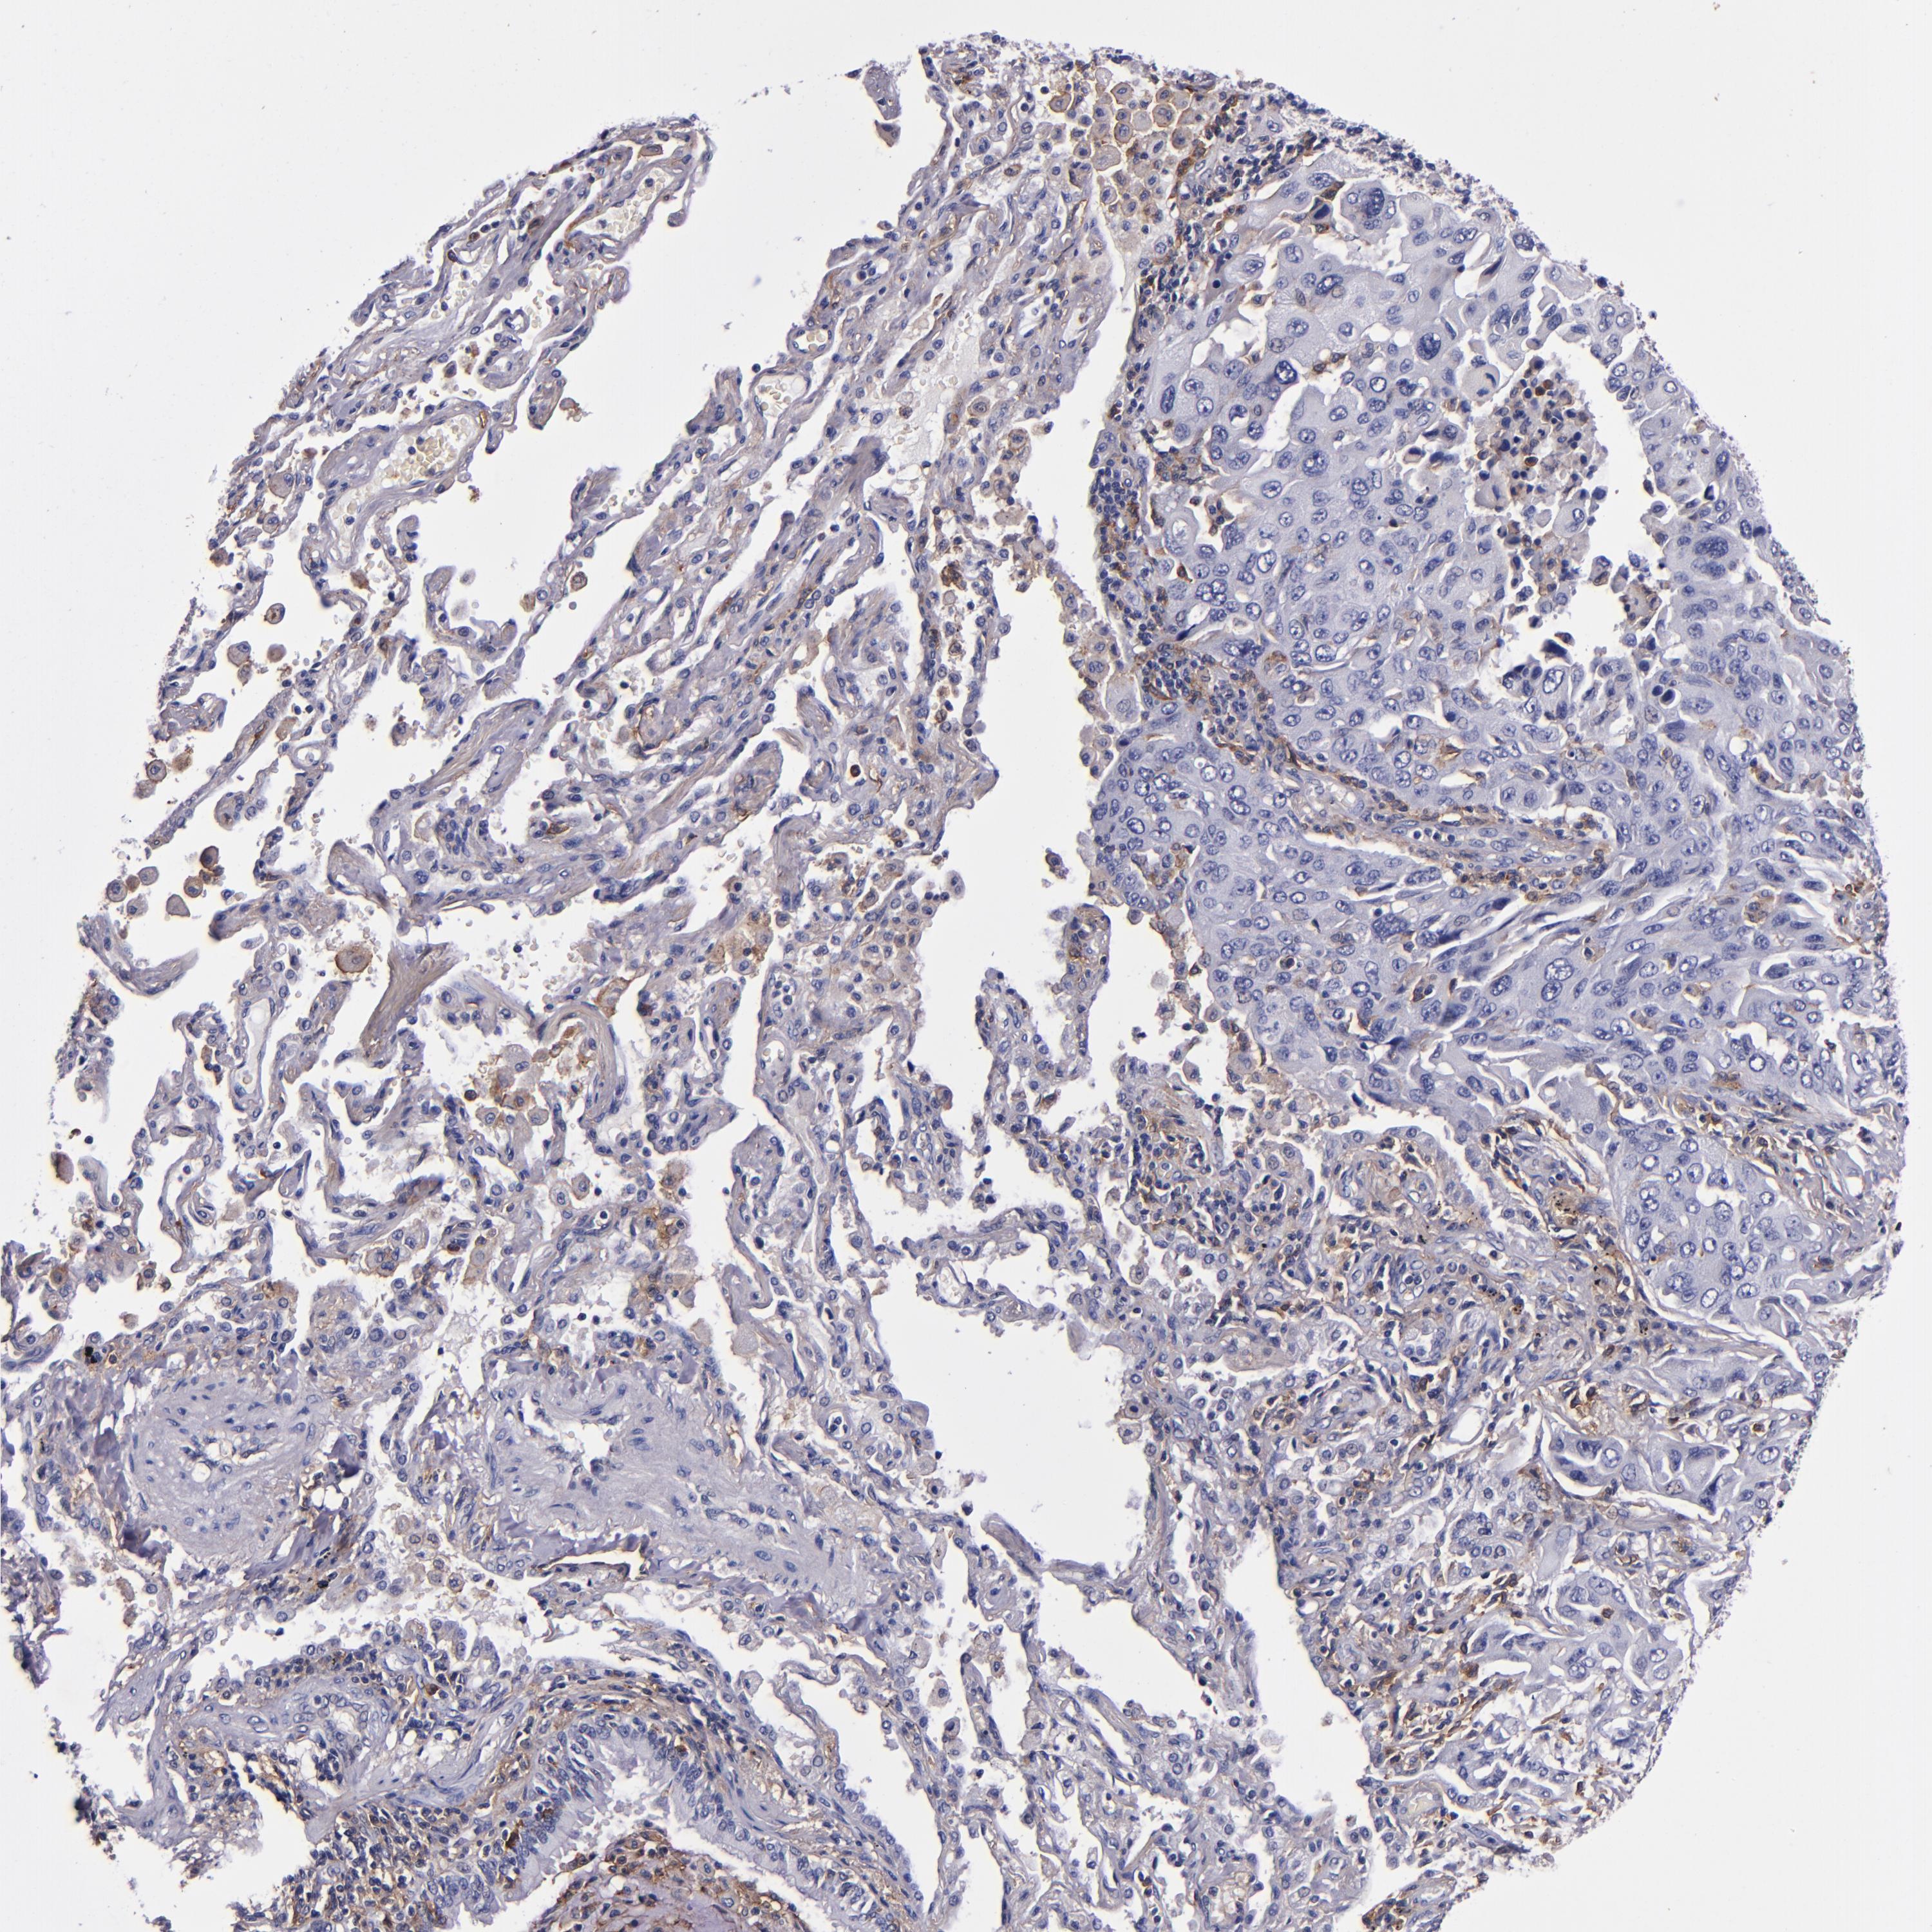

CANCER LUNG CANCER Show tissue menu

LUAD TCGA LUAD VALIDATION LUSC TCGA LUSC VALIDATION PROTEIN LUAD CPTAC PROTEIN LUSC CPTAC PROTEIN EXPRESSION